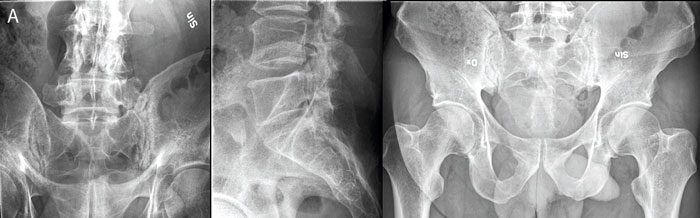

Medicinsk kommentar Röntgen av ländryggen är ett bra exempel

Översikt MRT och DT ger bättre och billigare resultat